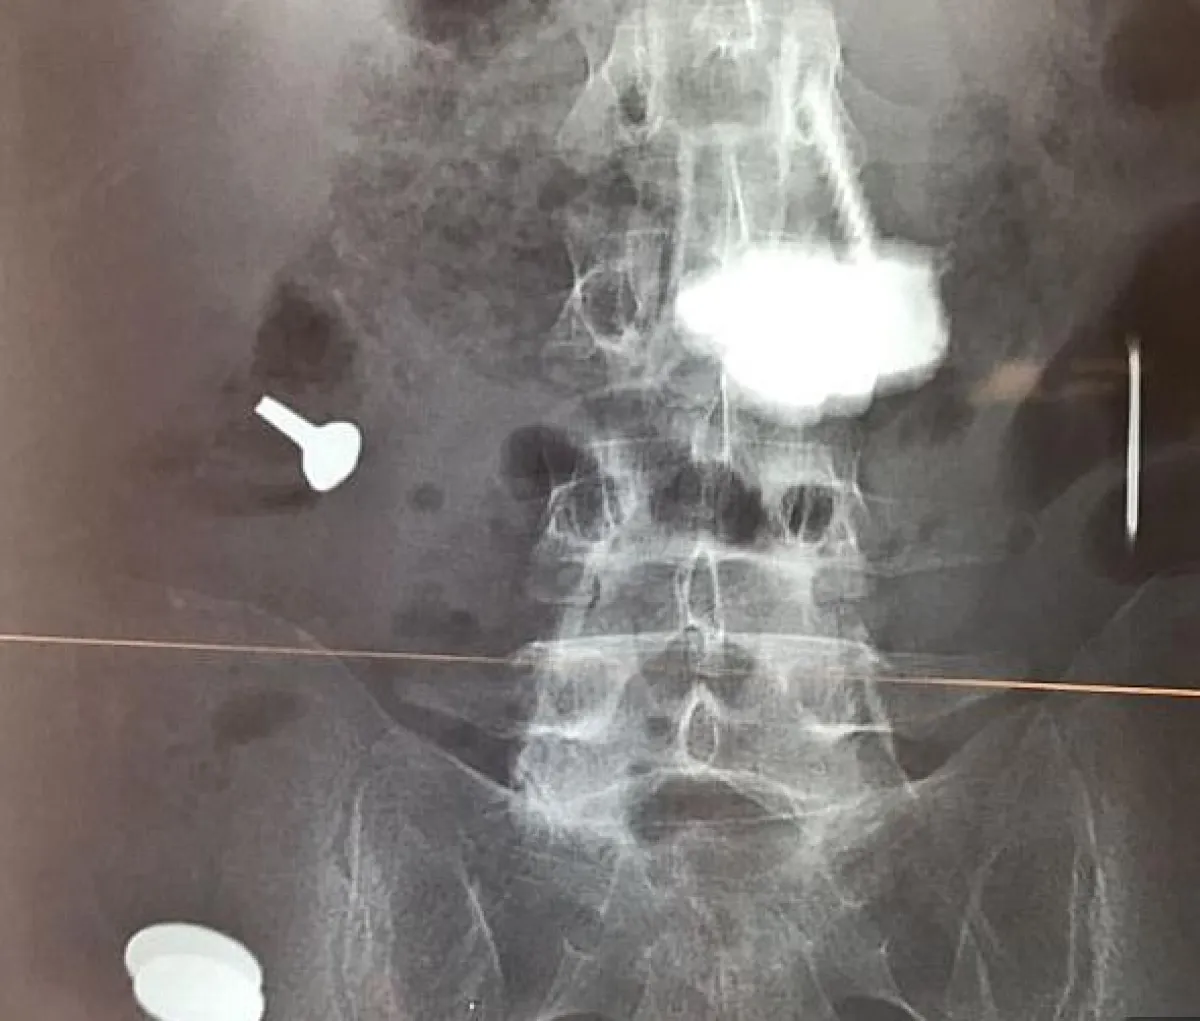

وتم نقل المريض إلى الطوارئ مرات عدة، وخضع لـعمليات على مدى 5 سنوات، لأنه كان يتقيّأ دمًا ويتعرض لألم شديد، نتيجة وجود هذه الكتل في بطنه. وأُجريت له خمس عمليات لإزالة المسامير والسكاكين، والمكسرات، ورأس مفك البراغي، بالإضافة إلى مقابض المعالق والحصى، وأسلاك الحديد والعملات المعدنية، من بطنه.

وكان الرجل قد ذهب إلى المستشفى لأول مرة، في مايو 2012، وفقًا لـ"الديلي ميل"، حيث ظهرت لديه علامات انسداد مخرج المعدة، ما دفع الأطباء لإزالة البازهر عبر التنظير.

وبعد 8 أشهر، نُقل المريض إلى المستشفى للسبب نفسه، ثم خضع للجراحة، حيث وجد الأطباء آثارًا للمسامير والسكاكين، والأدوات الحادة الأخرى في بطنه.